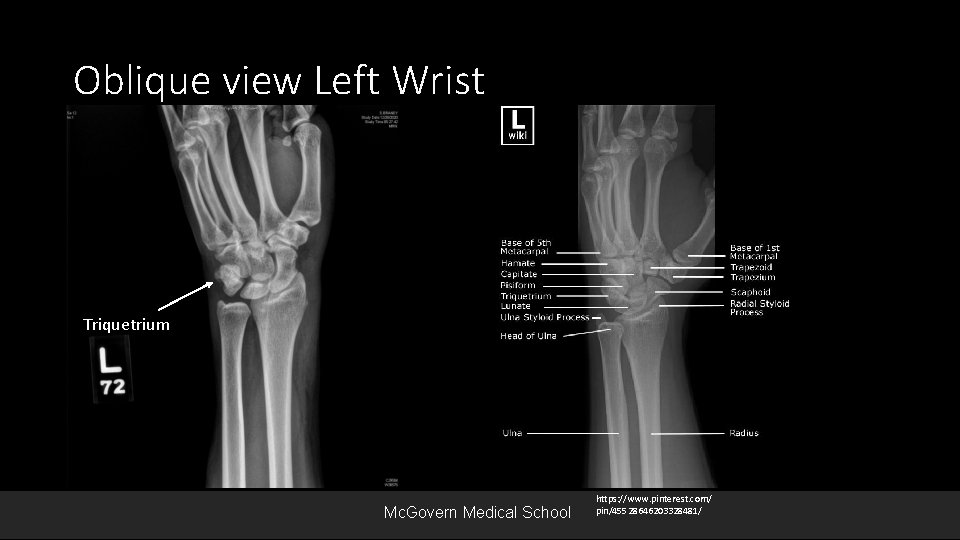

Oblique view Left Wrist Triquetrium Mc. Govern Medical School https: //www. pinterest. com/ pin/45528646203328481/